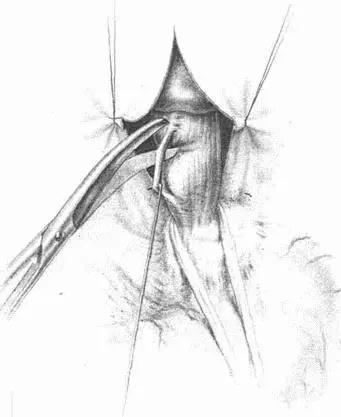

Рис. 71.Тотальная гастрэктомия. Треугольная связка левой доли печени

Рис. 72.Пересечение венечной связки при мобилизации левой доли

Рис. 73.Обкалывание нижней диафрагмальной вены

Рис. 74.Рассечение диафрагмы между двумя лигатурами

Рис. 75.Сагитальная диафрагмотомия. Мобилизован пищевод

Рис. 76.Сагитальная диафрагмотомия. Анестезия и пересечение левого блуждающего нерва

Рис. 77.Сагитальная диафрагмотомия. Пересечение левого блуждающего нерва

Рис. 78.Рассечение серозного покрова тонкой кишки, указывающего место наложения швов-держалок, и наложение первого шва на тощую кишку и пищевод